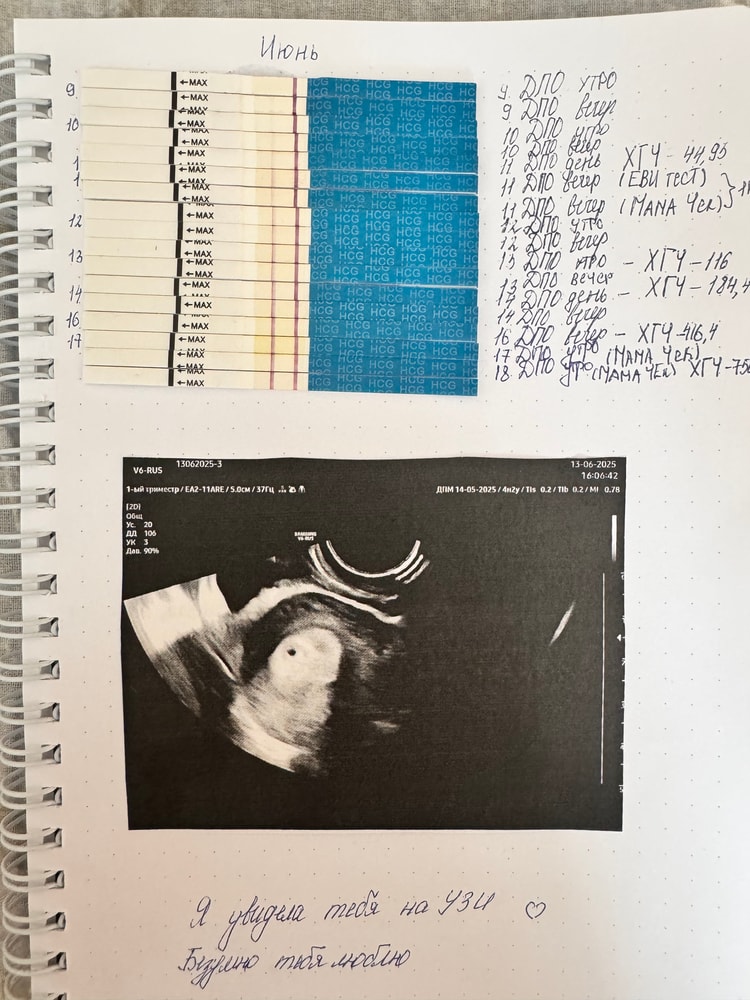

УЗИКороче, накрутила я себя вчера до слез, что ХГЧ в 1,8 вырос за 48 часов, плюнула, записалась на УЗИ, чтобы исключить ВБ. Пришла к 15:30, но пришлось подождать пол часа, т.к задержали. Легла на кушетку, объяснила причину почему пришла, мне сказали, что ещё могут ничего не увидеть, даже внематочную. Я уже смирилась, что ничего не увидят, лежу, молю бога, чтобы все было нормально, а через минуту мне врач говорит «У вас маточная беременность, можете успокоиться» и показывает бусинку. Я расплакалась от счастья, так как это 1 беременность, которую обнаружили на УЗИ из 4 беременностей. Врач посмотрела дальше, сказала угроз нет, тьфу тьфу тьфу, эндометрий 16 мм, ПЯ не деформировано , все хорошо. Я хорошо так выдохнула, так как меня врач ещё успокоила насчет ХГЧ , сказала, что за 2 суток рост 1,5-2 раза это норма, он может рости скачками и также назначила на повторное узи через 10-14 дней, чтобы увидеть ЖМ и эмбриончик. Я шла домой с улыбкой на лице, обрадовала мужа. Теперь дома режим хрустальной вазы, стараюсь кушать и много отдыхать. А грудь так и осталась сдутой но болючей, живет короче своей жизнью. Также последний тест сегодня, поярчал, больше не мурыжу ни себе, ни малышу нервы. Так что девочки, не отчаивайтесь, бог всегда даст, когда прийдет время 💕🥰